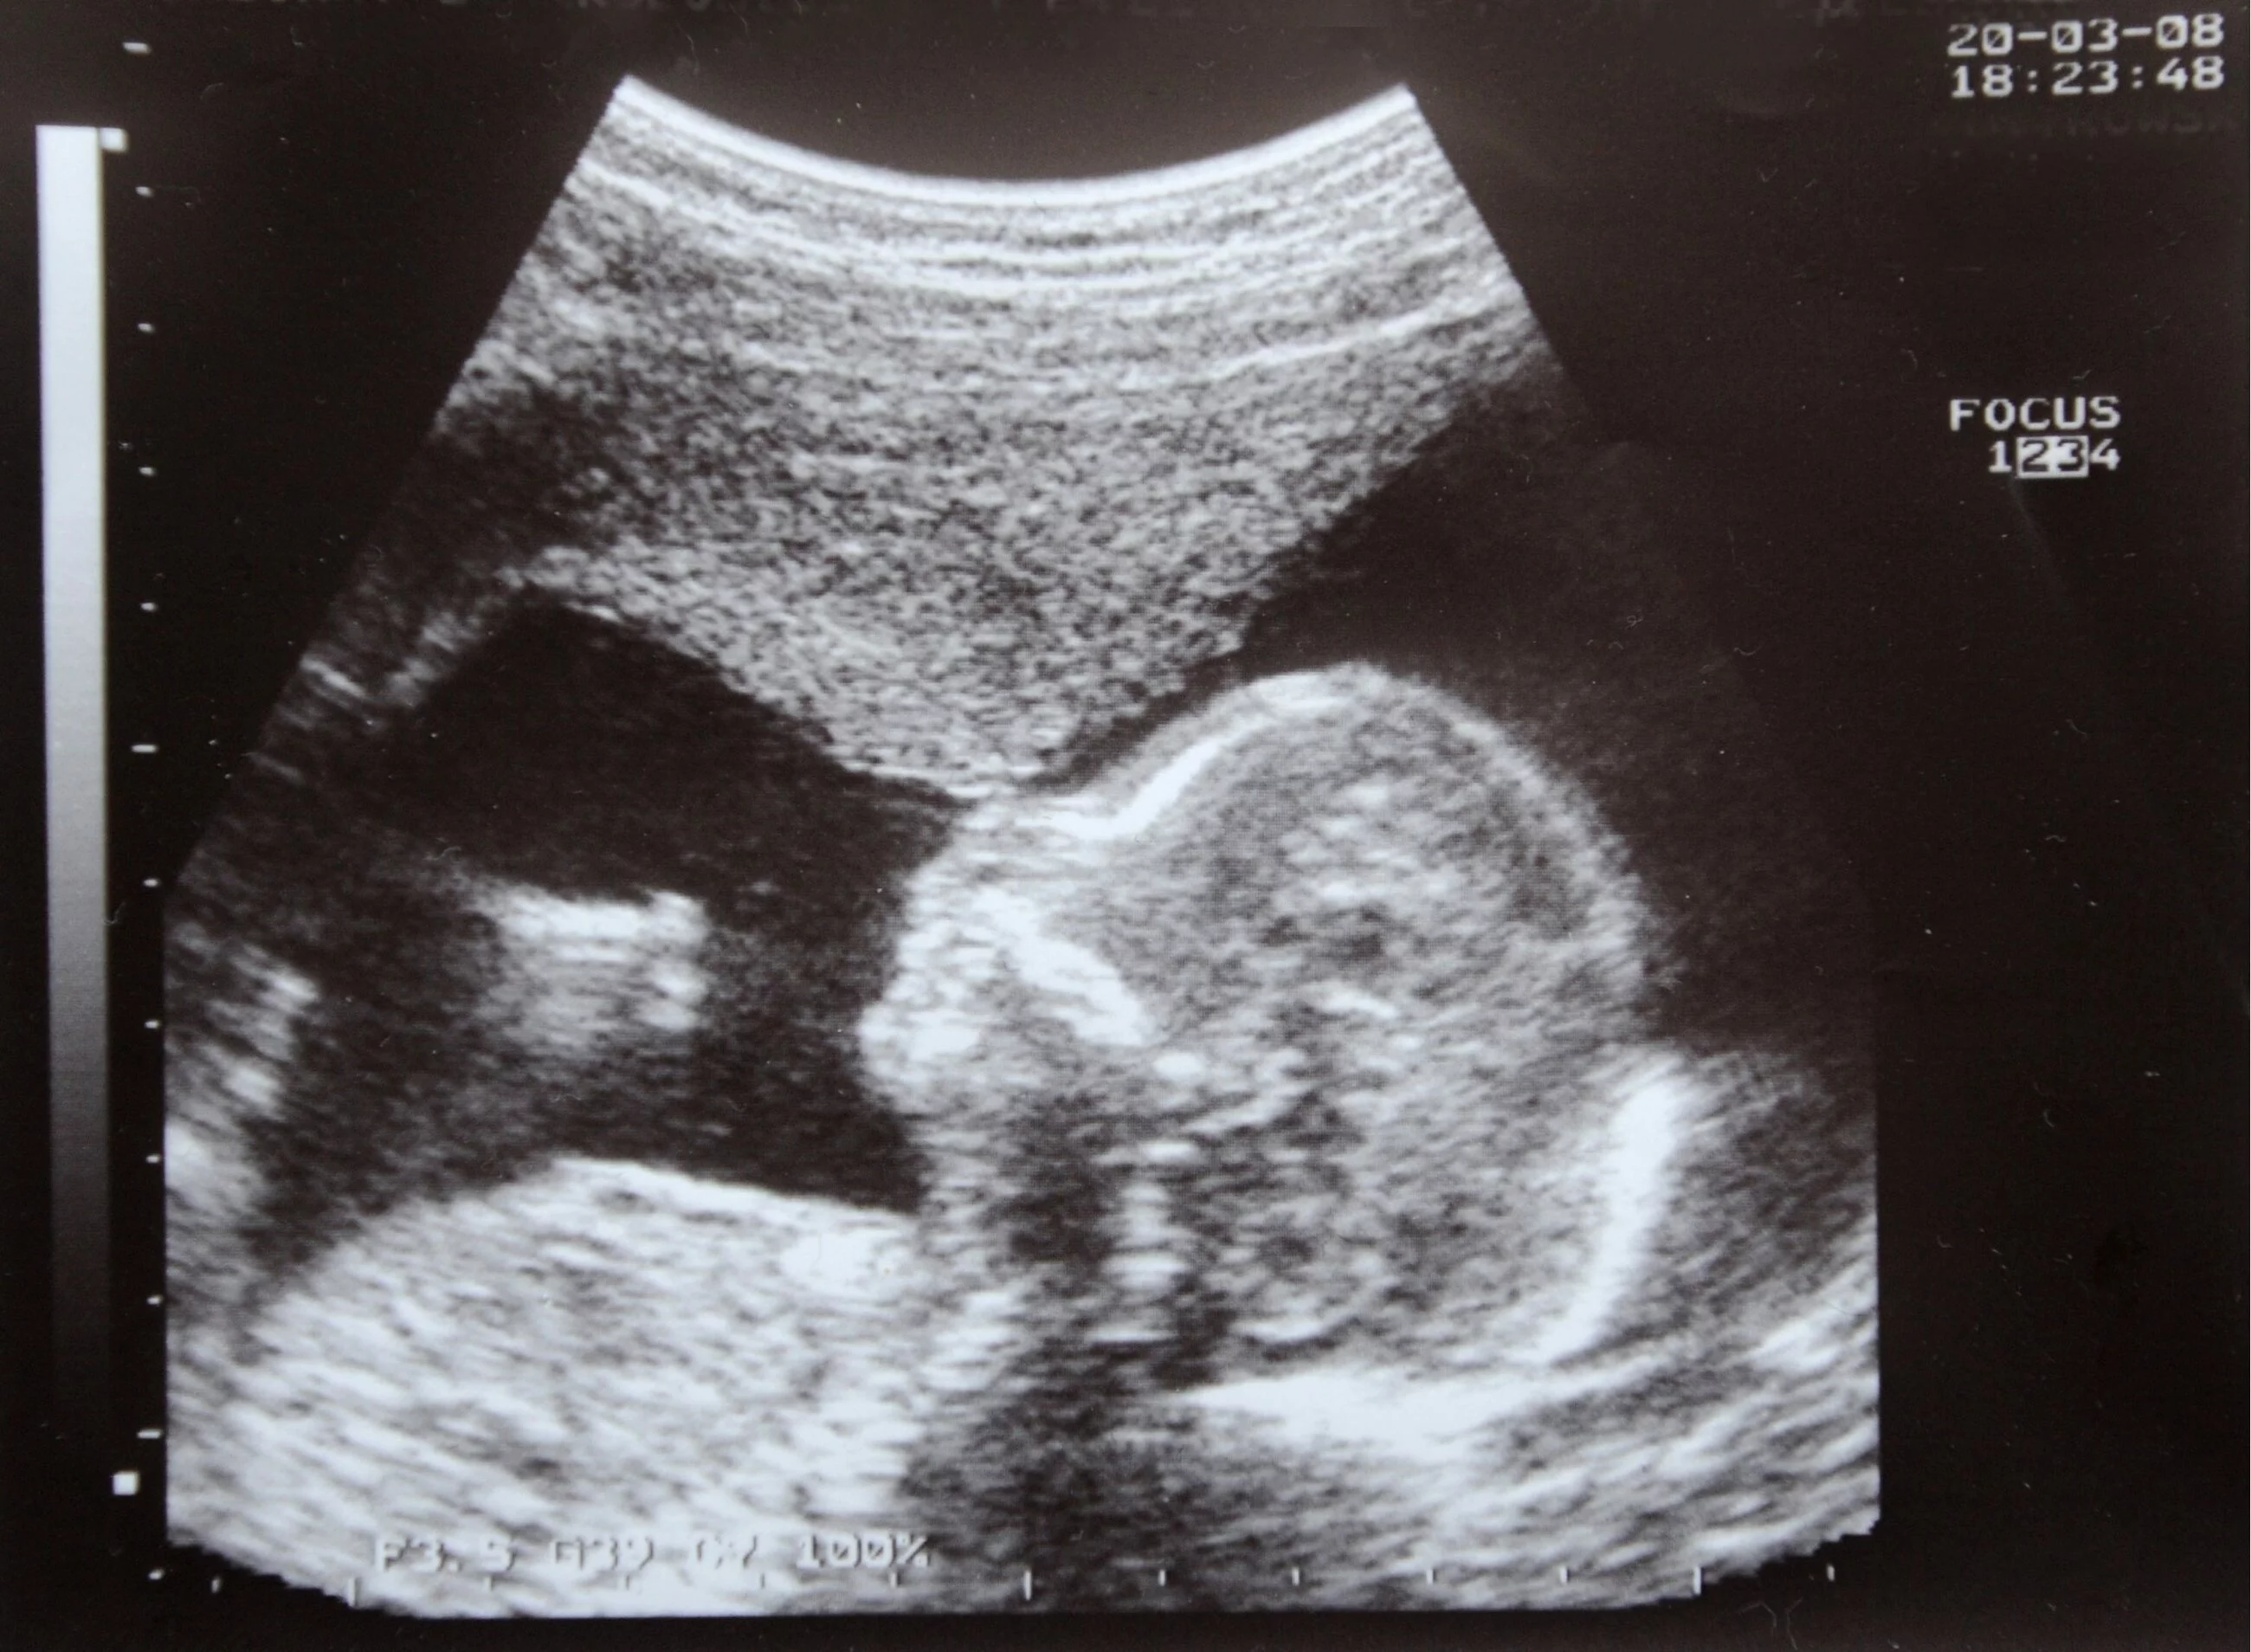

74,6 proc. ankietowanych popiera dopuszczanie legalnego przerwania ciąży, jeśli na podstawie badań wiadomo, że dziecko urodzi się z poważnymi wadami; jednak tylko 65,5 proc. badanych popiera legalną aborcję, jeśli na podstawie badań wiadomo, że dziecko urodzi się z poważnymi wadami z wyłączeniem zespołu Downa.

Jak wynika z sondażu, za prawem do przerwania ciąży, kiedy zagrożone jest życie dziecka, jest 69,1 proc. badanych.

Dwa tygodnie temu Trybunał Konstytucyjny ogłosił wyrok w sprawie zgodności z konstytucją aborcji eugenicznej. Orzeczenie zapadło większością głosów. Sędziowie Leon Kieres i Piotr Pszczółkowski zgłosili zdanie odrębne do wyroku. – Przepis zezwalający na dopuszczalność aborcji w przypadku dużego prawdopodobieństwa ciężkiego i nieodwracalnego upośledzenia płodu albo nieuleczalnej choroby zagrażającej jego życiu jest niezgodny z konstytucją – orzekł Trybunał Konstytucyjny.